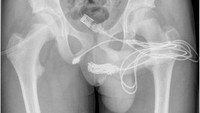

Seorang pria di Samarinda, Kalimantan Timur, mengalami kesakitan yang luar biasa setelah memasukkan benda asing ke dalam penisnya. Menurut laporan yang dipublikasikan di Radiology Case Reports, pria tersebut memasukkan benda seperti alat ekstraktor kartu SIM, kabel listrik, hingga karet gelang. (Foto: Radiology Case Reports).